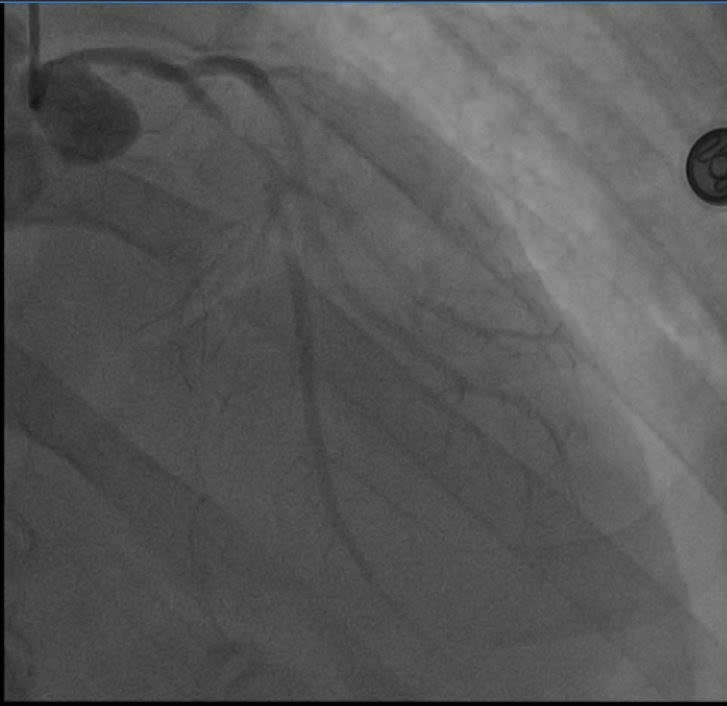

Các bác sĩ thực hiện can thiệp mạch vành qua da (PCI) cho người bệnh. Kết quả chụp mạch số hóa xóa nền (DSA) xác định tổn thương hẹp khít 99% đoạn gần nhánh liên thất trước (LAD) – vốn được mệnh danh là "động mạch của sự sống". Các bác sĩ tim mạch can thiệp đã nhanh chóng triển khai kỹ thuật đặt Stent, giải phóng điểm tắc nghẽn, tái lập dòng chảy mạch vành để cứu vãn vùng cơ tim đang thiếu máu cục bộ cấp tính và ngăn chặn các cơn loạn nhịp nguy hiểm.

Tim bị hẹp tắc được can thiệp thành công - Ảnh BVCC